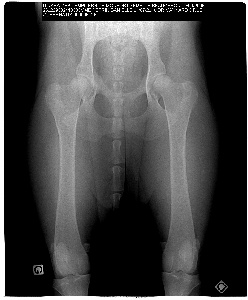

Voici la radio de Dee-leyme qui est actuellement en lecture